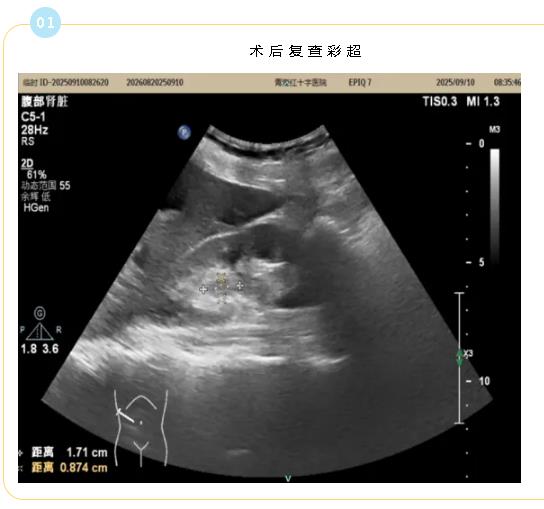

术后复查彩超

术后恢复情况:术后第二日患者恢复情况良好,精神状态佳,各项指标均未见明显异常,未出现任何并发症。在医护人员的指导和家属的陪伴下,患者顺利下床活动。复查泌尿系彩超,右肾盂内未见明显积液,肿瘤消融术后改变,在确认无出血、无漏尿后已拔除肾盂引流管,解除了患者身上的“束缚”,患者及家属表示就是一个针眼解决了大问题,这种极致的微创,极大地减少了身体创伤及痛苦,也最大程度地降低了感染和出血的风险。整个恢复过程,患者未经历传统手术后的剧痛,生活质量显著提高。术中穿刺活检进一步进行了免疫组化检测,为后续治疗提供最精确的导航。